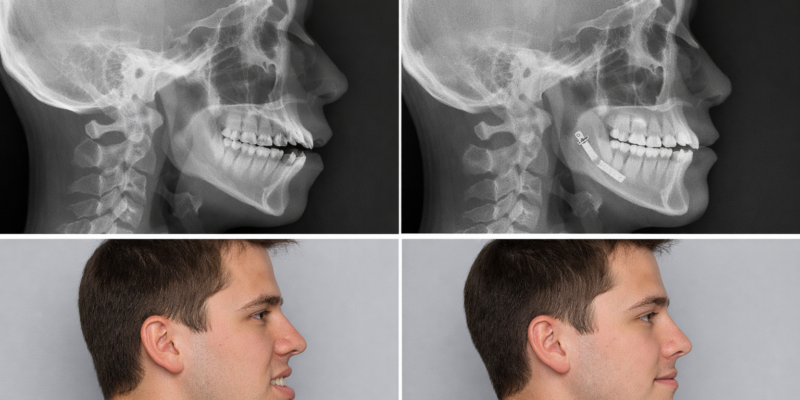

En el área de la cirugía ortognática, corregimos y modificamos las deformidades de maxilares y del perfil facial: prognatismo o exceso mandibular, mentón y pómulos; además de conseguir la oclusión idónea en cada paciente, o dar solución a una posible apnea obstructiva del sueño. Una de las innovaciones del servicio es la Rinoplastia con ultrasonidos incorporada por la Dra. Susan Díaz Reverand que supone importantes ventajas frente a otras técnicas más convencionales, ya que el postoperatorio es más confortable para el paciente porque presenta menor inflamación, menos hematoma y resulta mucho más indoloro.

Cirugía ortognática